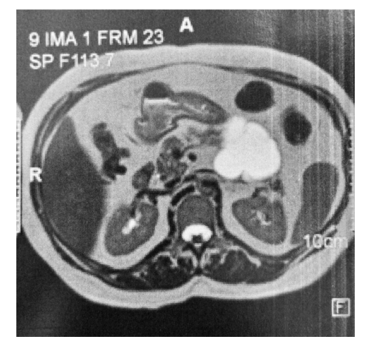

Um homem de 52 anos de idade apresenta a lesão pancreática assintomática mostrada a seguir.

Com base nesse caso hipotético, é correto afirmar que a lesão menos provável com relação ao diagnóstico final é o(a)